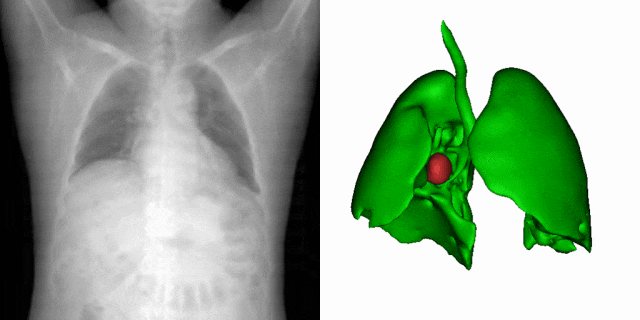

当前,深度学习在影像引导靶区定位和分割中的应用,多受训练数据量的制约。虽然通过优化网络结构可以在某个特定任务上达到优良的性能,但网络的泛化性却受到了牺牲。面对数据的稀缺性。研究团队提出了一种新型的基于统计形变的三维医学影像数据扩增法。该方法通过对不同病患的解剖空间变化进行建模,以有限的数据集中的形态信息,产生物理上真实反映病患器官变化的图像。如图1所示,一幅原始病患影像,经过此形变模型处理,便可衍生出多种器官的解剖结构。在多个公开数据集的实验中,这一方法展现了最好的靶区定位与分割效能。研究成果以A statistical deformation model-based data augmentation method for volumetric medical image segmentation为题,发表在医学影像分析顶刊Medical Image Analysis (IF=10.9)。客座本科生何文丰为第一作者,梁晓坤副研究员为通讯作者。

图1:研究团队提出的基于统计形变模型的三维医学影像数据扩增法的实现效果